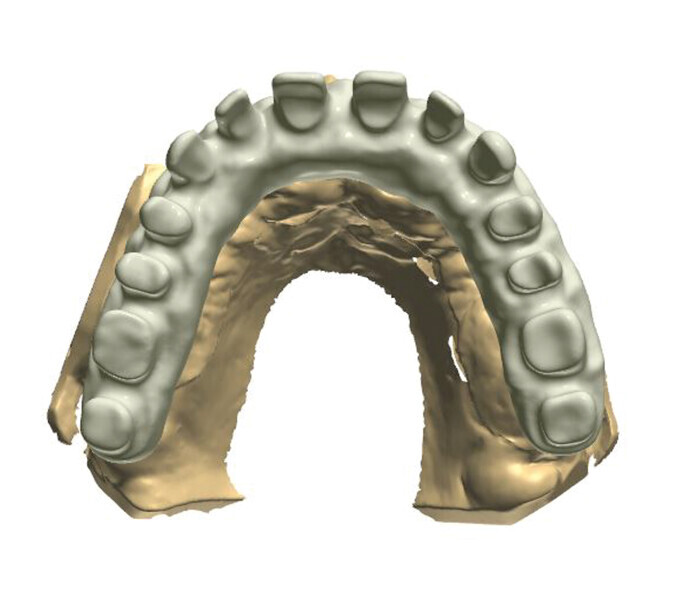

Fig. 3: Ready-made construction on a virtual model.